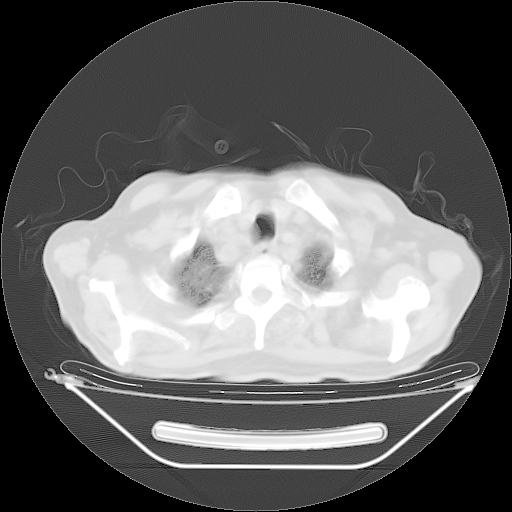

今天复查肺部CT,发现双肺广泛磨玻璃样改变。所以我把3月19日和5月9日相隔50天的肺部CT上传。请大家会诊。

2009年3月19日肺部CT片。

2009年3月19日肺部CT

5月9日肺部CT(在4月27日齐鲁医院肺部CT描述部分肺组织磨玻璃样改变,12天后肺组织广泛磨玻璃样改变)

大致读了系列胸部CT:纵隔窗无明显异常,肺窗:从4、27至今:主要是双肺中下野外带可见毛玻璃样改变,目前处于急性肺泡炎阶段,至于原因考虑1、结替组织或胶原血管性疾病所致?2、恶性疾病如恶组在肺部所致的表现或细支气管肺泡癌?3、药物或其它原因如肺蛋白沉着症所致肺泡炎目前不太可能?总之,明天就去请我院的呼吸科、感染科、血液科和临免专家会诊哈。